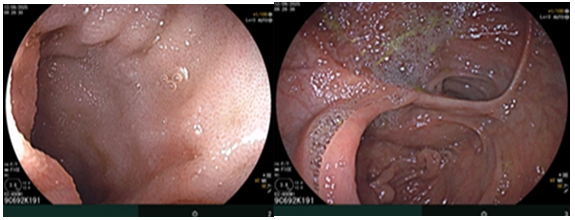

Tháng 01/2025 Bệnh nhân ở nhà xuất hiện mỏi, vàng da, ngứa kèm sốt kéo dài một tháng, đợt này đau bụng mạn sườn phải, kèm vàng da tăng dần, đi khám ở bệnh viện tuyến dưới, siêu âm có sỏi đường mật gan trái kích thước 22x41mm. Bệnh nhân được chuyển đến bệnh viện Bạch Mai và được chụp CT ổ bụng phát hiện, kết quả:  Gan có kích thước bình thường, bờ đều,  nhu mô hạ phân thuỳ IV có ổ tổn thương dạng dịch kích thước 40x53mm, trong có sỏi lớn đường kính 35mm.

Hình 1. Hình ảnh sỏi đường mật tạo ổ áp xe gan - đường mật gan trái (vòng tròn màu đỏ). Giãn nhẹ đường mật trong gan hai bên. Dày thành nhẹ ngã ba đường mật trên phim chụp cắt lớp vi tính.